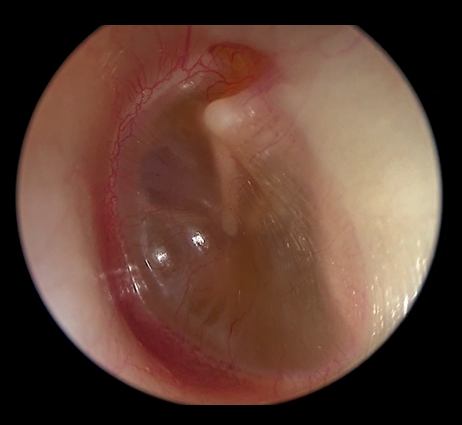

O diagnóstico da OME é feito no consultório durante o exame dos ouvidos. A otoscopia, exame físico dos ouvidos, revela um tímpano opaco, com presença de líquido visível atrás da membrana e, eventualmente, retraído e avermelhado. Em casos duvidosos, a timpanometria, é um exame essencial, pois mostra a mobilidade do tímpano. Resultados do tipo curva B (curva achatada) sugerem presença de acúmulo de líquido.